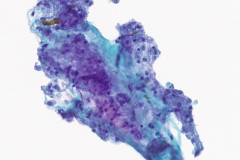

Cytologic Diagnosis: Negative for malignant cells, acute inflammation, multinucleated giant cells, few poorly formed granulomas, iron pill fragments.

Cytology:

Initial diagnosis of IPA is not always readily distinguishable on cytology examination of slides. There may be a presence of a small amount of yellow-brown material on modified Romanowsky and Papanicolaou stains which without the clinical history of aspiration could easily be interpreted as non-specific artifact or other types of pigmented particles such as hemosiderin or carbonaceous particles.6 Histological examination of biopsy material is typically the gold standard for diagnosis, wherein iron pill injury is characterized by the presence of crystalline iron fibrils in the presence of necrosis or in an ulcer base.1 An iron stain such as Perls’ Prussian Blue can aid in determining the iron composition of the yellow-brown material by staining iron as a bright blue color.9 Microscopic features of the biological response to the aspiration exposure may include the presence of multinucleated giant cells, hemosiderin-laden macrophages, granulomas, and reactive atypia of squamous metaplasia. Care should be taken when assessing the Prussian Blue stain results as the hemosiderin in macrophages will also stain positively.9